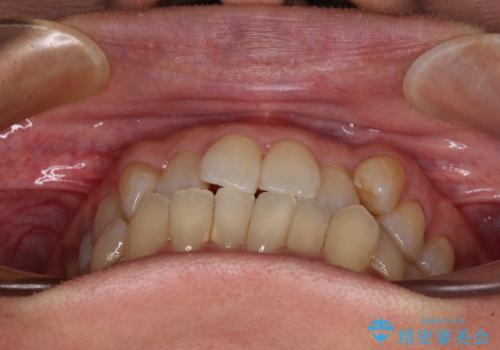

受け口と八重歯を改善 インビザライン矯正治療

- 前歯のデコボコや八重歯を治したいとのことで来院された患者様です。

受け口傾向の骨格であり、前歯はクロスバイトまたは切端咬合となっており、下顎を中心に歯列全体の後方移動を行い、IPR(歯と歯の間を削る)によってデコボコが解消するように設計し、インビザラインにより治療を行うこととしました。

受け口傾向のインビザライン矯正は比較的治療を行いやすいため、きれいに仕上げることができました。舌の突出癖が顕著であったため、改善のためのトレーニングをしっかりと行っていただきました。